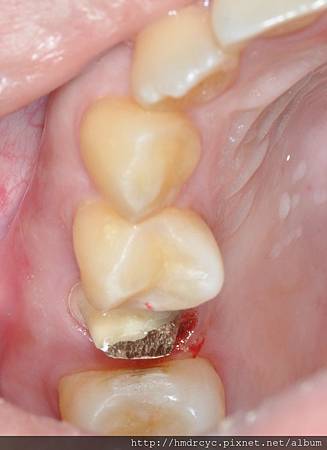

先製作牙鑄心

裝入牙鑄心後

金屬色部分就是重建的結構